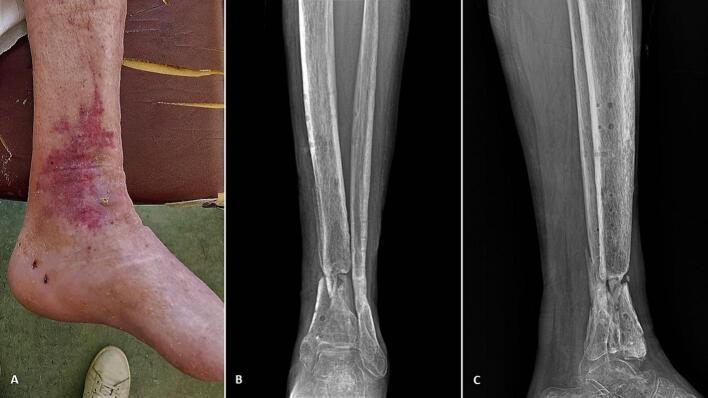

The management of septic non-unions with associated bone necrosis is challenging, especially when the resulting bone defect after the debridement is extensile. Different techniques have been described in the literature for the treatment of these demanding cases, with the most prominent being free vascularized Fibular graft and bone transport with distraction osteogenesis principles. Recently, 3D printing technology has been increasingly utilized in many complex orthopaedic pathologies. However, the application of those advancements regarding septic non-unions with residual bone defect has not been previously studied. This study presents a novel 3D printing technique for the management of an infected critical bone deficit of the tibia. Queries, challenges and future perspectives concerning the recruiting of 3D printing technology in limb reconstruction are also being discussed. Clinical Evidence Level: IV.

伴有骨坏死的感染性骨不连的治疗具有挑战性,尤其是清创后出现的骨缺损范围较大时。文献中描述了多种治疗这些复杂病例的技术,其中最突出的是游离带血管腓骨移植和采用牵张成骨原理的骨搬运。近年来,3D打印技术在许多复杂的骨科疾病中得到了越来越广泛的应用。然而,这些进展在伴有残余骨缺损的感染性骨不连中的应用尚未得到过研究。本研究提出了一种用于治疗胫骨感染性严重骨缺损的新型3D打印技术。同时也讨论了在肢体重建中引入3D打印技术的相关问题、挑战及未来展望。临床证据等级:IV级。